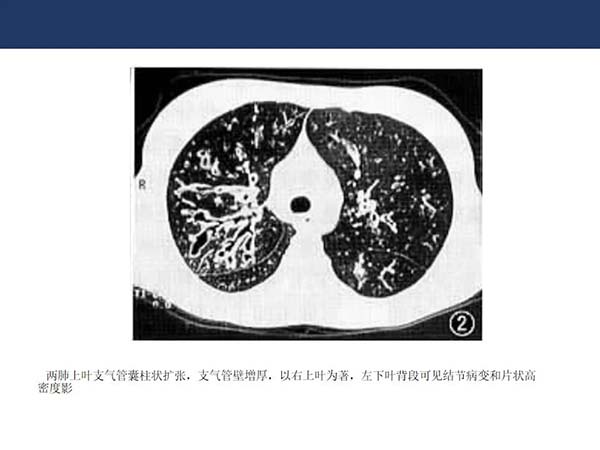

【杨柳病例】非结核分支杆菌肺病(NTMPD)